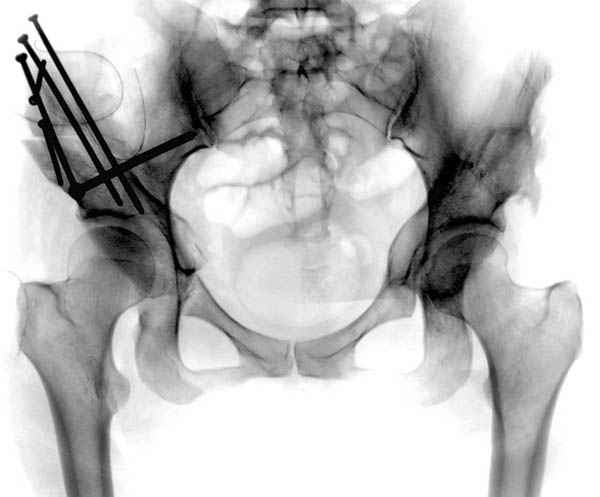

Картина типичной эволюции дисплазии сустава "кистовидная перестройка", на фоне неправильного взаймоотношения сустава "да тут угол Виберга 0 градусов" на вершине наибольшей нагрузки в вертлужной впадине образовался участок разрежения, "киста", в последующем через этот участок образуется перелом - стадия фрагментация дисплазии.

Для установки диагноза достаточно информации, на рентгенограмме передний и задний край ацетабулум образовали перекрест, "цифру восемь", указывающий на небольшую ретроверсию, а суставная щель одинаковой ширины на всем протяжении, что доказывает, что с покрытием хряща проблем нет. Головка бедра покрыта всего наполовину, это явное нарушения взаимоотношений.

В развитых ортопедических центрах после дисплазии в молодом возрасте для сохранения сустава периацетабулярная остеотомия стала стандартом лечения.

Как я отметил, даже "для больного 40 лет (с оптимистическим расчетом на ревизионное эндопротезирование через 15 лет) это важно" мы бы рекомендовали коррегирующию периацетабулярную остеотомию с ревизией сустава и остеопластикой импинжмента шейки.

Цель периацетабулярной операции - восстановление нормальных взаимоотношении в суставе, поэтому рекомендуемые остеотомии в молодом возрасте предназначены для профилактики дальнейшего разрушения сустава.

Кстати, после остеотомии и удаления нагрузки от проекции кист в нашей серии были самостоятельное выздоровление кисты и зарастание фрагментированного участка стенки кисты даже после минимальной фиксации.